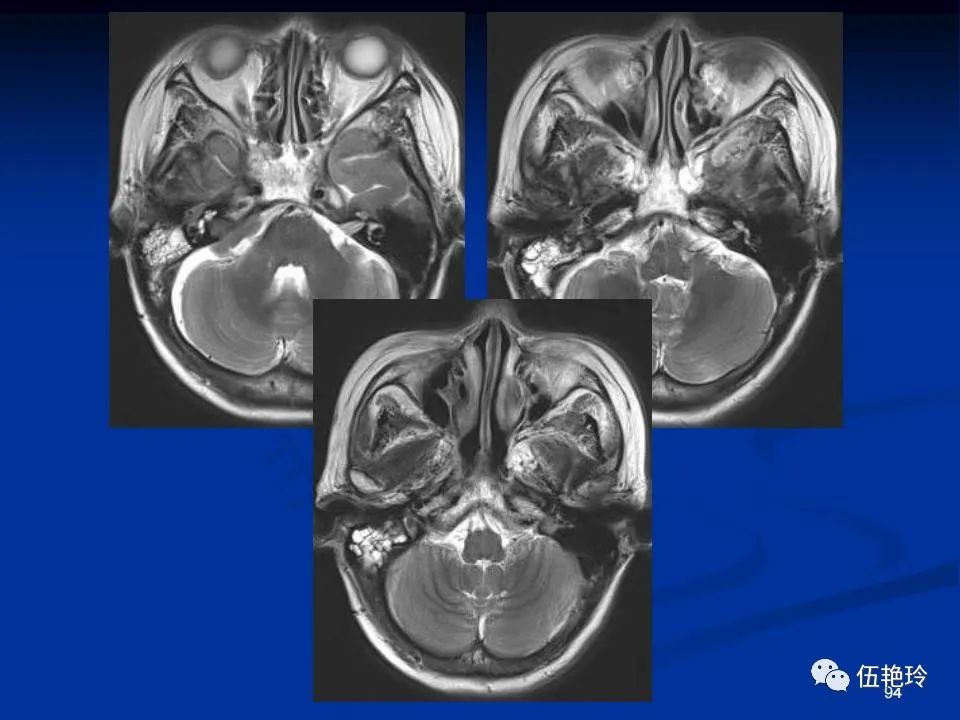

耳与面神经的解剖